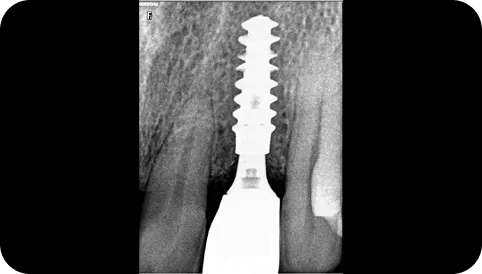

Digital X-rays

Accuracy is essential in modern dentistry, and we take that accuracy very seriously. Dental digital images today provide enhanced radiation safety levels and improved diagnostic performance. With digital imaging X-ray sensors are utilized which facilitates more chair-side time to devote in care of our dental patients.

Immediate Implants

We use superior products to give our patients natural-looking restorations that are designed to last a lifetime. Same Day Dental Implants in India with Nobel Biocare immediate implants are placed at the same time as the natural tooth is removed. This shortens time-to-teeth and reduces the number of visits, benefiting the patient. Our goal is to restore the tooth in an aesthetically pleasing and functionally successful way.

CBCT Planned Treatments

We at Smilex make the use of digital technology for treatment planning for a variety of cases. Dental cone beam computed tomography is used when we require three dimensional (3-D) images of your teeth, soft tissues, nerve pathways and bone in a single scan. This helps us to serve you better for treatments ranging from root canals to implants and wisdom tooth removal.